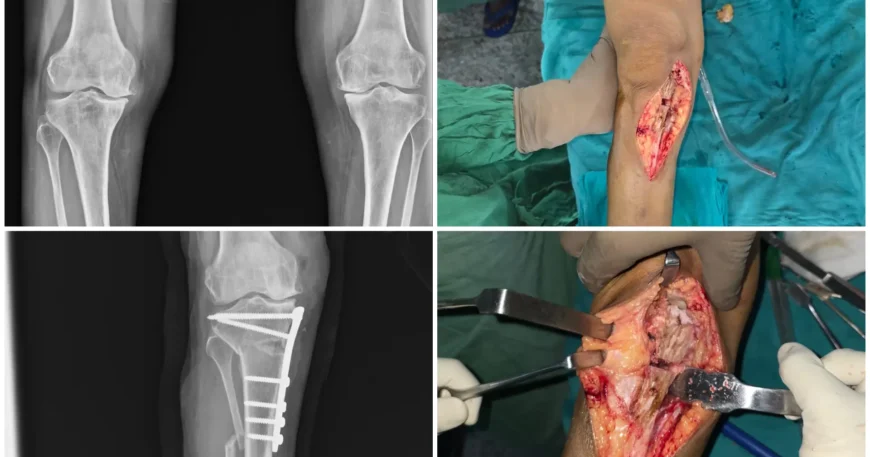

Medial Compartment Osteoarthritis of Right Knee Successfully Treated with High Tibial Osteotomy

Considering her age, activity level, and localized nature of arthritis, the orthopedic team recommended High Tibial Osteotomy (HTO) — a joint-preserving surgical procedure.

High Tibial Osteotomy (HTO) with Plates and Screws

Mrs. Amramma underwent High Tibial Osteotomy, a procedure designed to:

The correction was stabilized using plates and screws, ensuring precise alignment and proper bone healing.